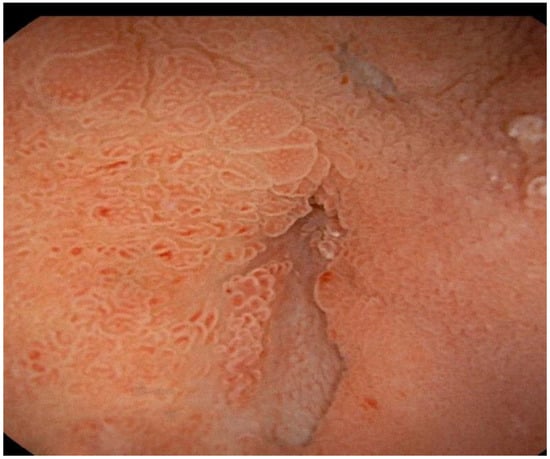

Approximately two months after the hospitalization, they returned to the hospital with epigastric pain and fever (38 °C). Laboratory results showed a WBC count of 14,530/mm3 (neutrophils: 78%) and a CRP level of 163 mg/L (<5 mg/L), procalcitonin 0.14 ng/mL. Pancreatic enzymes and liver function test results were within the normal ranges. An abdominal CT scan showed the presence of multiple confluent fluid collections extending from the head to the tail along the entire pancreatic profile containing air (Figure 1). An endoscopic investigation and an endoscopic ultrasound (EUS) were performed. The upper endoscopy revealed the presence of a fistula opening of about 8 mm in diameter in the duodenum bulb with leakage of purulent material (Figure 2). EUS showed the presence of air in the fistula and a complex 5 cm fluid collection in the tail of the pancreas (Figure 3). An abdominal CT scan with gastrografin confirmed the fistulous channel originating from the first duodenal portion, which gives rise to two branches, anteriorly in the head of the pancreas and posteriorly in the tail. After a collegial reunion with clinicians, surgeons, radiologists, and gastroenterologists, it was decided to proceed with the drainage of the larger pancreatic collection in an attempt to heal the fistula with the duodenum. EUS-guided trans gastric drainage of the fluid collection was performed using a 16 × 20 mm lumen-apposing metal stent (LAMS, Hot-Spaxus, Taewoong Medical Co., Gimpo, Korea), obtaining drainage of copious purulent material in the stomach (Figure 4).

Figure 2.

Endoscopy view of fistula opening of about 8 mm in diameter in the duodenum bulb with leakage of purulent material.